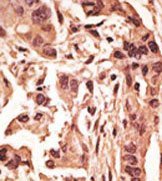

Supportive validation

- Submitted by

- Acris Antibodies GmbH (provider)

- Main image

- Experimental details

- Formalin-fixed and paraffin-embedded human cancer tissue reacted with the primary antibody, which was peroxidase-conjugated to the secondary antibody, followed by DAB staining.